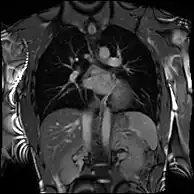

Combined with vasodilator stress it has a role in detecting and characterizing myocardial ischemia due to disease affecting the epicardial vessels and microvasculature. Late gadolinium enhancement (LGE) and T1 mapping allow infarction and fibrosis to be identified for characterizing cardiomyopathy and assessing viability.[7] Magnetic resonance angiography may be performed with or without contrast medium and is used to assess congenital or acquired abnormalities of the coronary arteries and great vessels.[8]

Conventional phase contrast imaging can be extended by applying flow-sensitive gradients in 3 orthogonal planes within a 3D volume throughout the cardiac cycle. Such 4D imaging encodes the velocity of flowing blood at each voxel in the volume enabling fluid dynamics to be visualised using specialist software. Applications are in complex congenital heart disease and for research into cardiovascular flow characteristics - however it is not in routine clinical use due to the complexity of post-processing and relatively long acquisition times.[25]